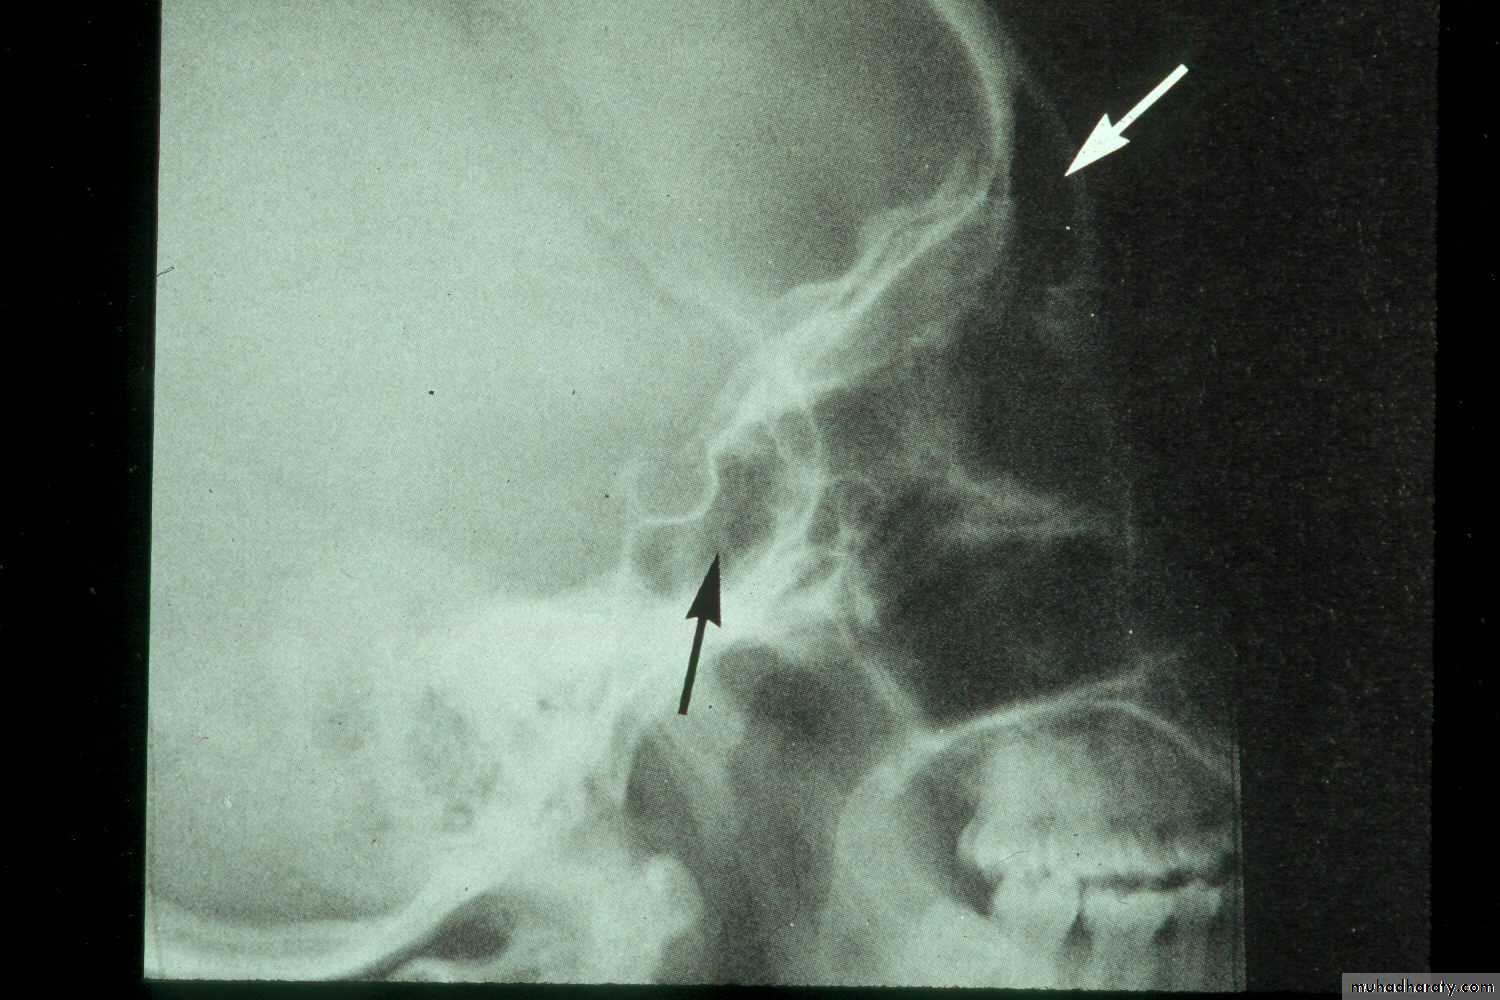

• Lateral Skull: (i) confirming the presence of fluid level and cyst (ii) in localizing a foreign body, e.g. root; particularly when the foreign body is located higher up in the sinus.

Lateral view of normal frontal and sphenoid sinuses